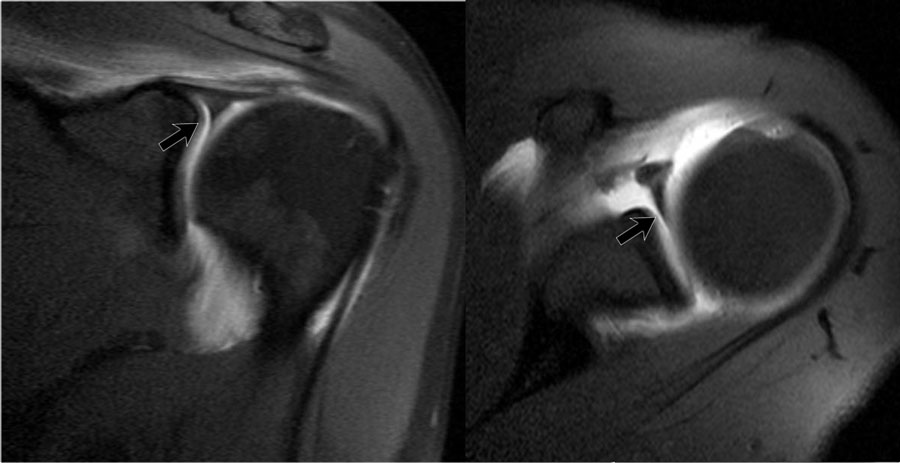

Tư thế ABER

Rách sụn viền

Tư thế dạng tay-xoay ngoài (ABER) rất hiệu quả trong việc đánh giá sụn viền trước-dưới ở vị trí 3-6 giờ,

nơi hầu hết các trường hợp rách sụn viền xảy ra.

Ở tư thế ABER, dây chằng ổ chảo-cánh tay dưới bị căng ra, tạo lực kéo lên sụn viền trước-dưới, cho phép thuốc tương phản từ nội khớp thấm vào giữa vị trí rách sụn viền và ổ chảo.

Rách chóp xoay

Tư thế ABER cũng rất hữu ích cho cả rách chóp xoay một phần lẫn toàn bộ chiều dày.

Động tác dạng tay và xoay ngoài giải phóng sức căng trên chóp xoay so với mặt cắt vành tiêu chuẩn khi cánh tay ở tư thế khép.

Kết quả là, các vết rách một phần chiều dày nhỏ ở mặt khớp sẽ không bị áp sát vào các thớ sợi còn nguyên vẹn liền kề của chóp xoay

cũng như không bị che khuất bởi chỏm xương cánh tay, và thuốc tương phản từ nội khớp có thể giúp hiển thị rõ hơn vị trí rách (3).

Hình ảnh ở tư thế ABER được thu nhận theo mặt phẳng ngang, lệch 45 độ so với mặt phẳng vành (hình minh họa).

Ở tư thế đó, vùng 3-6 giờ được chụp theo mặt phẳng vuông góc.

Lưu ý mũi tên đỏ chỉ một tổn thương Perthes nhỏ, không thấy được trên các mặt cắt ngang tiêu chuẩn.